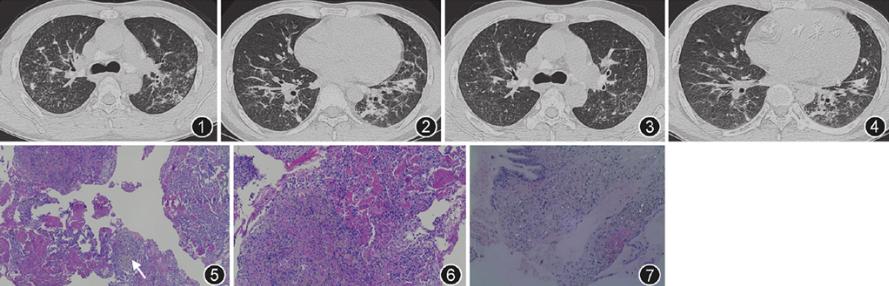

患者男,31岁,磨石工人,因"反复咳嗽、咳痰3年,气喘半年,加剧伴发热7 d"于2013年6月27日入院。患者入院3年前反复咳嗽,痰为白色黏液样。半年前症状明显时痰转为黄色黏液样,伴活动后气喘、发热,体温最高达39.5 ℃,发热前无寒战,多次就诊当地县级医院,给予"哌拉西林/他唑巴坦+左氧氟沙星抗感染"等治疗(具体不详),症状可好转,但易反复。既往体健。从事打石行业10余年,工作环境中粉尘多,卫生条件差。吸烟10年,20支/d。父亲死于"矽肺"。体检:体温37.8 ℃,口唇无发绀,双肺呼吸音粗,双中下肺可闻及散在湿性啰音,未闻及干性啰音,无胸膜摩擦音。辅助检查:血常规示白细胞为14.52×109/L,中性粒细胞比率为75.5%,嗜酸粒细胞比率为0%。ESR为48 mm/1 h。C反应蛋白为78.7 mg/L。肝肾功能正常。降钙素原、痰涂片抗酸染色(3次)、痰培养、血培养、血癌胚抗原、抗核抗体10项、血管炎组合、1-3-β-D葡聚糖及结核菌素试验均阴性。肺功能示轻度限制性通气功能障碍。胸部CT(2013年7月4日)提示纵隔及双肺门多发淋巴结肿大伴钙化,双肺多发斑片状阴影(图1,图2)。气管镜下见气管及双侧各支气管黏膜充血、轻度水肿,管腔通畅,见少量浅黄色泡沫样分泌物;刷检涂片抗酸染色(3次)、BALF致病菌培养、灌洗液半乳甘露聚糖试验(GM试验)均阴性;活检病理提示:(左下肺)肺组织间质慢性炎细胞浸润;灌洗液涂片(左下肺)见多量吞噬颗粒异物的巨噬细胞。行CT引导经皮肺穿刺,病理提示:(左下肺)符合尘肺合并机化性肺炎。给予吸氧、亚胺培南/西司他丁(0.5 g/0.5 g静脉滴注,8 h/次)抗感染及解痉、化痰等处理,病情无好转。肺穿刺病理提示尘肺合并性机化性肺炎后,停用抗生素,加用甲泼尼龙(40 mg静脉滴注,1次/d)抗炎治疗,症状明显好转。复查胸部CT(2013年7月13日)示双肺斑片状阴影部分吸收(图3,图4)。转请北京协和医院病理科会诊读片,诊断为急性纤维素性机化性肺炎(图5,图6,图7),患者住院18 d后出院,出院继续全身激素治疗(泼尼松30 mg,1次/d,逐渐减量)。

图1,2第1次发作治疗前(2013年7月4日)胸部CT可见双肺多发斑片状渗出实变影,以左下肺明显

图3,4第1次发作糖皮质激素治疗后(2013年7月13日)胸部CT可见双肺病灶部分吸收好转

图5肺泡腔内见嗜伊红的纤维素样物沉积形成纤维素球,其内部或周边见新生由纤维母细胞/肌纤维母细胞增生形成的息肉样结节交替分布HE低倍放大

图6纤维/肌纤维母细胞增生结节上见黑褐色粉尘样颗粒HE低倍放大

图7 偏光显微镜下机化结缔组织栓子内可见二氧化硅颗粒HE高倍放大